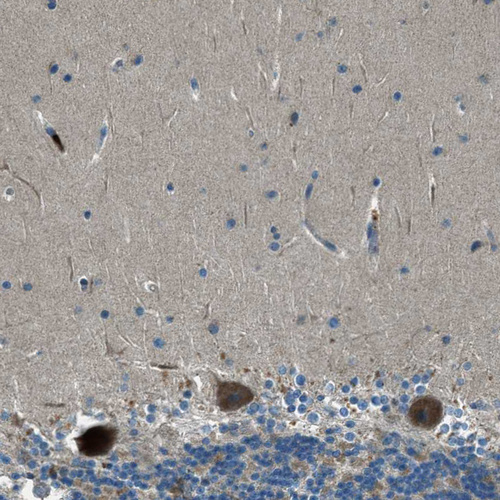

Immunohistochemical staining of human duodenum shows strong cytoplasmic positivity in glandular cells.